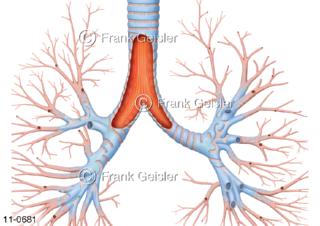

11-0681 Luftröhre Trachea eröffnet, Darstellung Bronchialbaum mit Bronchien